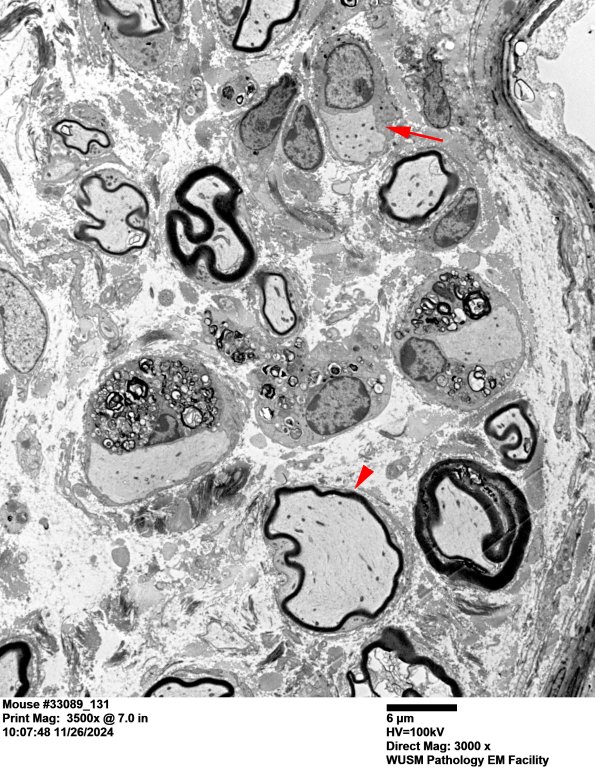

Case 2 This is a demyelinative neuropathy in a knockout mouse. ---- 2A1,2 This low magnification image of the peripheral nerve shows several axons which are demyelinated with Schwann cell myelin debris, another naked fiber with an adjacent Schwann cell without debris (arrow), presumably preparing to regenerate, and a thinly remyelinated axon (arrowhead). (electron micrographs)